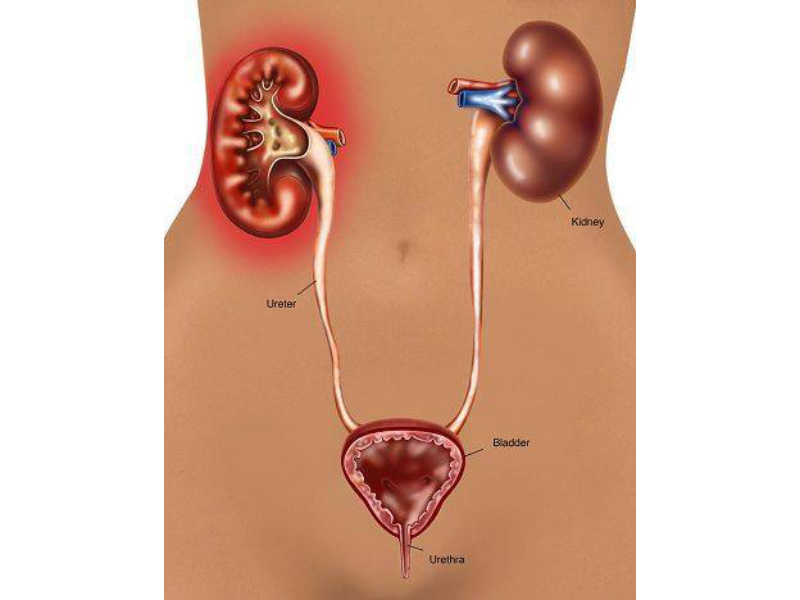

Kidney disease is also known as renal disease and nephropathy. It means damage to or disease in the kidneys. It may lead to loss of kidney function and kidney failure which is the end-stage of kidney disease. In severe cases, dialysis or a kidney transplant